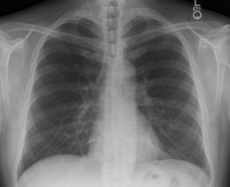

- Chest X-ray – can be used to image any problems or abnormality in lung pathology (e.g. pleural effusions etc).

- Computed Topography – can be used for an intensive and more detailed imaging of injuries and abnormalities in the anatomical pathology (e.g. detection of pulmonary emboli or airway tumor).